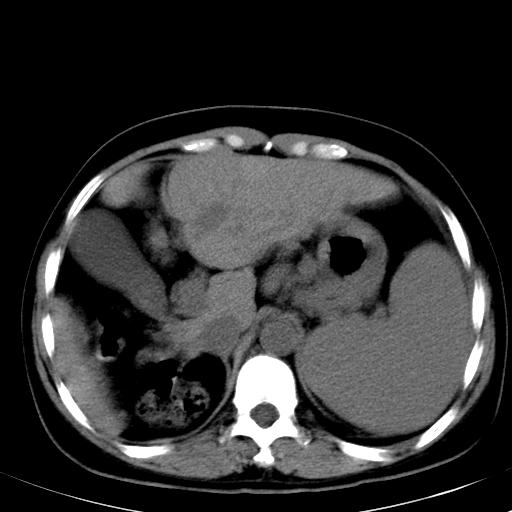

标题: CT19818:女40,脾大伴贫血,无肝炎病史 [打印本页]

标题: CT19818:女40,脾大伴贫血,无肝炎病史

血常规血红蛋白102,

骨穿,诊断再障,无其他病史

肝各叶比例失调,肝裂增宽,支持肝硬化\\脾大.

肝硬化、门脉高压、脾大。再障+肝硬化促成巨脾。

左肝大/右肝小,脾大,考虑肝硬化门脉高压,脾大。  不知是否有血吸虫感染病史

肝叶比例失调,肝左叶明显增大,包膜欠规整,脾大,支持考虑肝硬化、门脉高压、脾大。